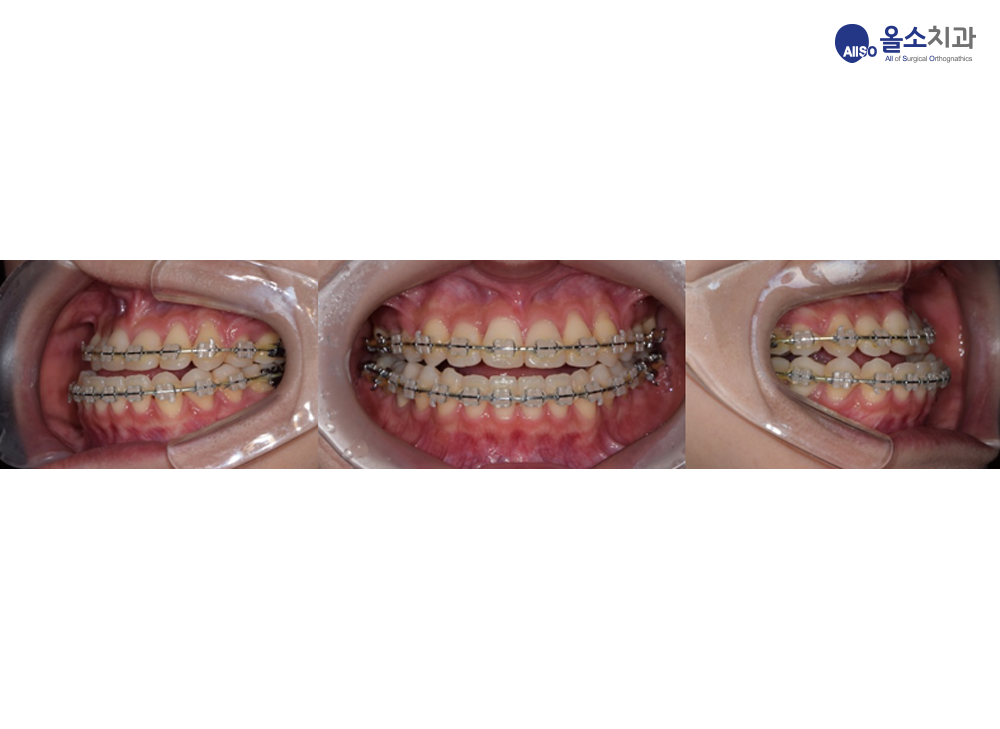

치아는 술전 교정을 받을 상태라, 주걱턱과 비대칭의 양을 치아에서도 그대로 보여주고 있습니다. 아래턱의 앞니가 위턱에 비해 앞으로 나와있고, 좌측으로 삐뚤어져 있습니다.

교합의 변화를 수술 전 교합 상태와 비교하여 보겠습니다.

수술 전에는 아래턱이 위턱에 비해 앞으로 나와있는 반대교합으로 위아래 앞니가 맞물리지 않으며, 좌우 비대칭이 심해 가운데 선이 맞지 않았습니다.